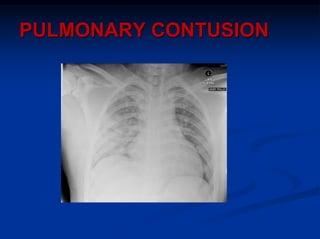

PULMONARY CONTUSION

Most common potentially lethal chest injury

Damage to parenchyma from passage shock wave

through tissue

CXR – may be normal, but usually shows opacity in lung

field, lags 12-24hr behind clinical picture

Respiratory failure subtle and develops over time. ABG

worsens at day 2-3 as oedema increases, careful

monitoring and reevaluation. Intubation and ventilation

if Sao2<90% especially if co- morbidities, or being

transported

In multi-injured trauma patient pulmonary contusion may

be superimposed by sepsis, SIRS, MODS, ARDS